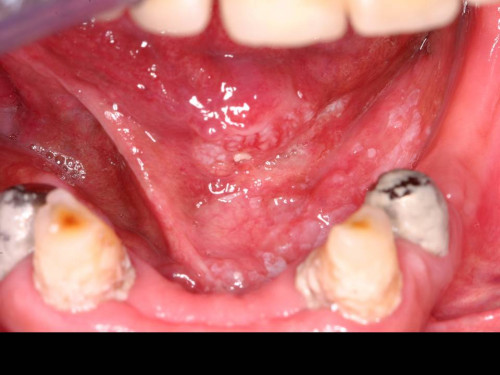

Mann mit linksseitigen Schmerzen an der Zunge

Ein 39-jähriger Patient stellt sich wegen Brennen und Schmerzen im linken Bereich der Zunge erstmalig in Ihrer Praxis vor. Die Symptome bestünden seit etwa drei Wochen. Ihre Fragen nach anderen Erkrankungen oder Medikamenteneinnahmen werden von dem Patienten verneint.

Welche Aussage des Patienten passt zu dem Befund, der sich Ihnen bei der intraoralen Inspektion zeigt?

- ANach einem Faustschlag vor 3 Wochen habe ich zunehmend Schmerzen.

- BIch rauche seit meinem 14. Lebensjahr und trinke zur Zeit ca. 0,5l Bier am Tag.

- CZur gleichen Zeit habe ich Blutbeimengungen im Stuhl bemerkt.

- DIch habe seit über 10 Jahren einen Knubbel an der Zunge, der jetzt auf einmal schmerzt.

- EVor 3 Wochen hatte ich eine geschwollene Wange und Fieber, seitdem tut mir die Zunge weh.

Makroskopie - intraoral präoperativ